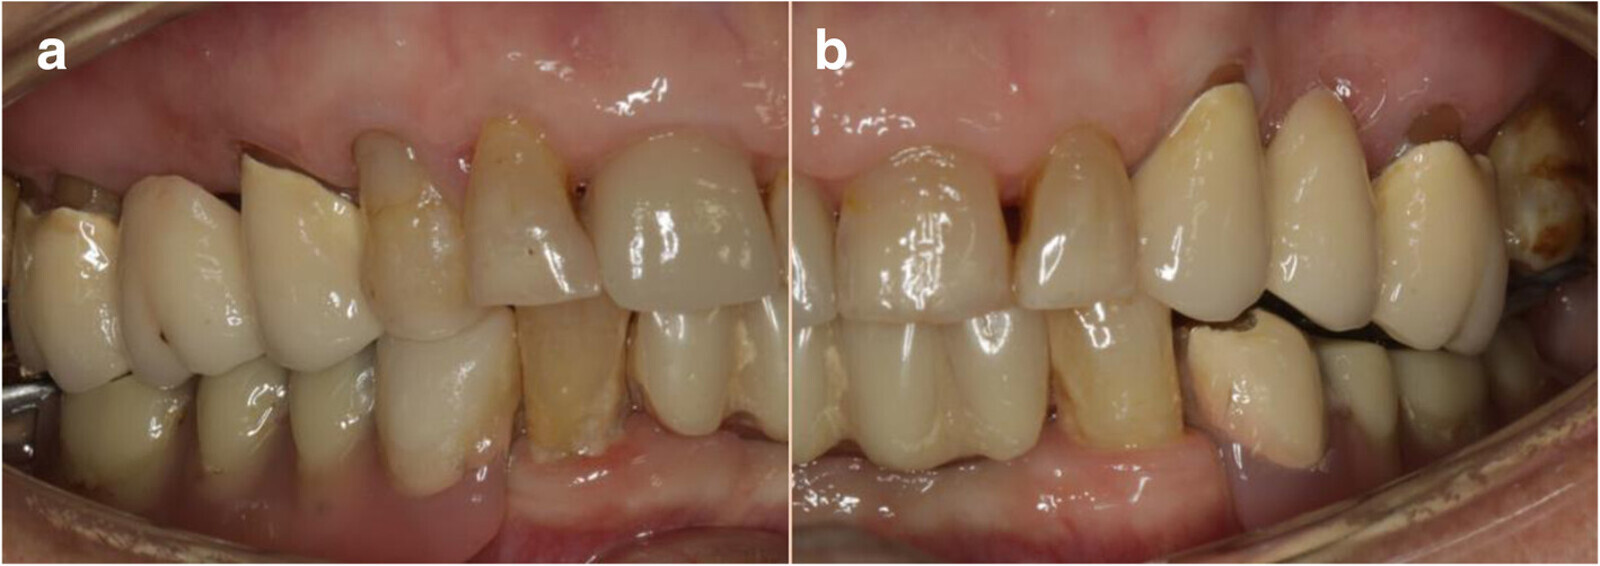

Figs. 2a & b: Initial dental status: right side (a) and left side (b).